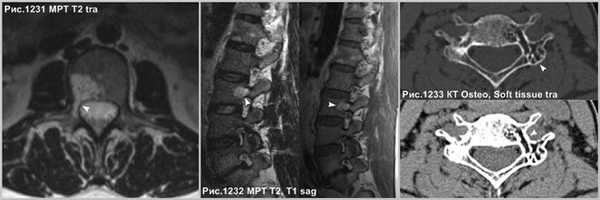

В случае нахождения гемангиомы в дужке или распространения с тела в дужку позвонка (головки стрелок на рис.1231-1233), важно указывать данный факт в связи с тем, что структура позвонка в указанном месте ослаблена и может послужить причиной патологического перелома в процессе медицинских манипуляций, так же важно учитывать этот факт нейрохирургам при транспедикулярной фиксации.

Иногда встречаются множественные гемангиомы, поражающие ряд позвонков, что может осложнить дифференциальную диагностику со вторичным, метастатическим поражением тел позвонков. Однако, гемангиомы имеют продольную исчерченность, что не встречается у метастазов. Гемангиомы возникают вблизи базивертебральной вены и, часто связаны с ней, и венами позвонка, так же гемангиомы часто имеют жировой сигнал, а метастазы расположены в телах позвонков хаотично и всегда, даже в случае склеротических очагов сопровождаются отёком костного мозга, свидетельствующем о реактивной костной реструктуризации и деструкции. Гемангиомы крайне редко распространяются за пределы тела пораженного позвонка, а метастазы весьма часто приводят к деформации тела позвонка, распространяются за его пределы. Кроме того, метастазы редко поражают исключительно позвоночник, сопровождаясь лимфоаденопатией узлов средостения, парааортальных, паракавальных групп, а так же возможна визуализация очагов в печени и лёгких, при анализе захваченных на сканировании областей.

![heangioma_7]()

Множественные гемангиомы, поражающие ряд позвонков (головки стрелок на рис.1234). Метастазы, поражающие тела позвонков (головки стрелок на рис.1235).